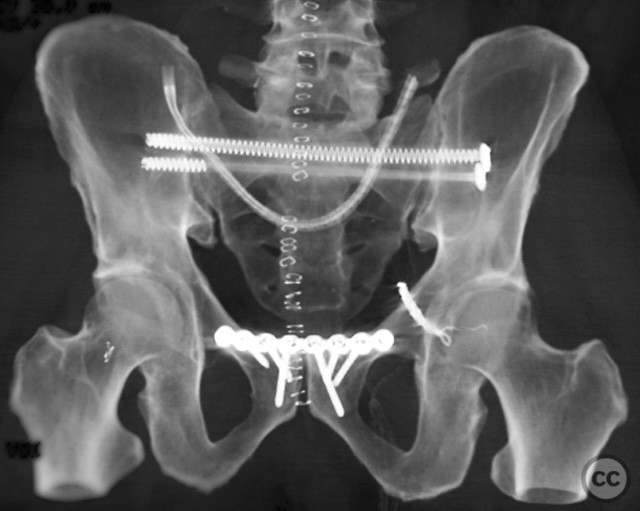

Clinical and radiological findings:  Middle-aged male involved in a motor vehicle accident sustained a complete symphysis pubis (SP) disruption and left sacroiliac (SI)/sacral combination fracture-dislocation (AO/OTA 61-C1.3). The patient presented with an open traumatic posterior pelvic wound. Initial assessment revealed hemodynamic instability requiring urgent laparotomy and subsequent angioembolization for pelvic hemorrhage. Axial CT imaging demonstrated significant displacement of the anterior and posterior pelvic ring, with embolic coils visible post-intervention.

Planning remarks:  The preoperative plan included staged fixation: initial supine positioning for low midline exposure and open reduction internal fixation (ORIF) of the pubic symphysis, followed by prone repositioning for irrigation and debridement (I&D) of the open posterior wound and stabilization of the posterior pelvic ring via iliosacral screw fixation under fluoroscopic guidance.

Patient positioning:  The patient was first positioned supine for anterior pelvic exposure and fixation, then repositioned prone for posterior wound management and fixation.

Anatomical surgical approach:  Anteriorly, a low midline infraumbilical incision was made to expose the symphysis pubis, with subperiosteal dissection of the rectus sheath and direct visualization of the disrupted symphysis. Posteriorly, a longitudinal midline approach over the sacrum was utilized, incorporating the traumatic wound for I&D. Deep dissection allowed access to the sacral ala and SI joint. A tenaculum clamp was applied percutaneously to achieve reduction of the sacral/SI fracture-dislocation. Iliosacral screws were inserted percutaneously under fluoroscopic control across the SI joint into S1.

The sequence of anterior then posterior fixation allowed unimpeded access to both injury sites. The use of a tenaculum clamp facilitated reduction of the complex posterior injury. No technical interference was encountered between anterior plate fixation and subsequent posterior iliosacral screw placement. The presence of embolic coils did not impede surgical access or reduction maneuvers.

Orthopaedic implants used:   3.5 mm anterior symphyseal plate, cannulated iliosacral screws